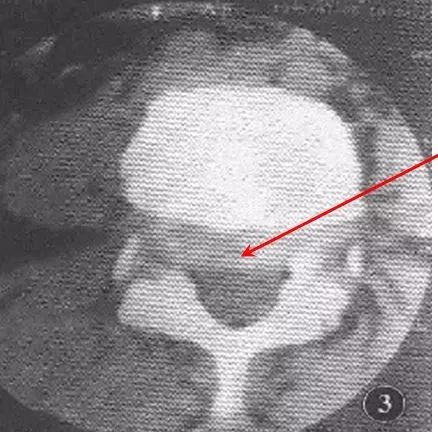

滑脱椎体"双边征"椎管前后径延长,可呈"双管征".

腰5至骶1节段椎管前后径加大,滑脱的腰5椎体前移,椎体后缘形成"双边征

椎管前后径延长"双管征"滑脱椎体"双边征"(三)腰椎mri片椎弓峡部层